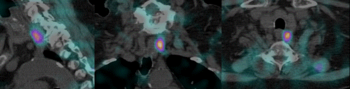

Exemples d’images obtenues par le service de Médecine Nucléaire de l’hôpital de Citadelle